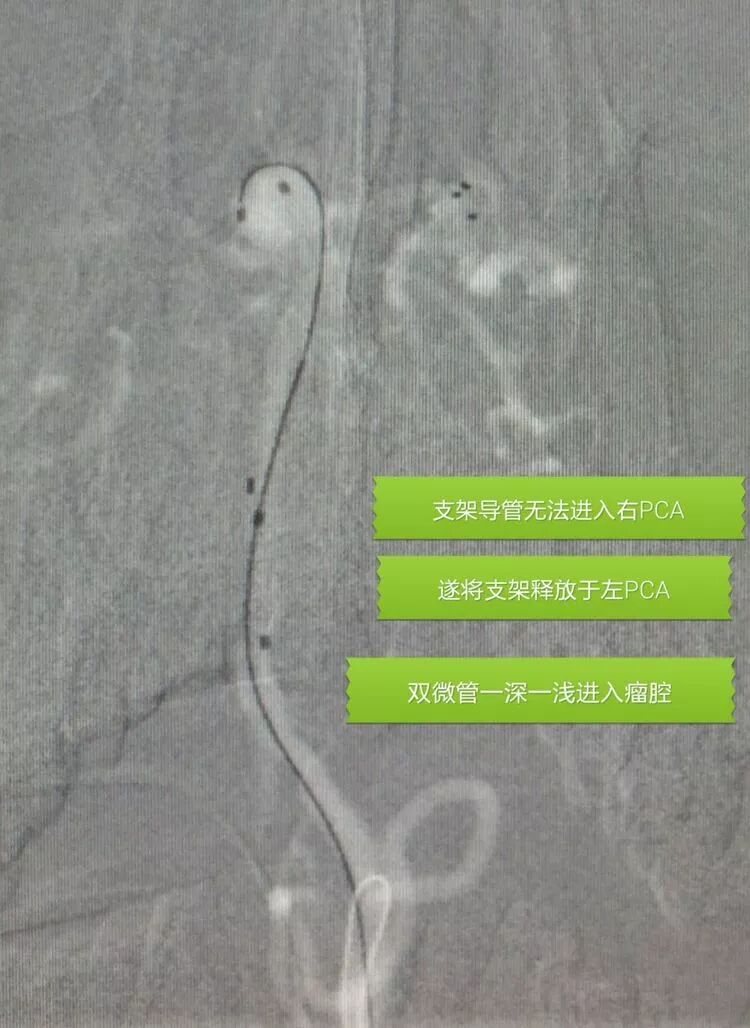

基底动脉顶端宽颈动脉瘤

应用Solitaire支架结合双微管栓塞,一根微导管是45°预塑形的,管头置于瘤体中央(浅管),另一根微导管管头塑成C形,沿瘤底深入到瘤体右侧角(深管)